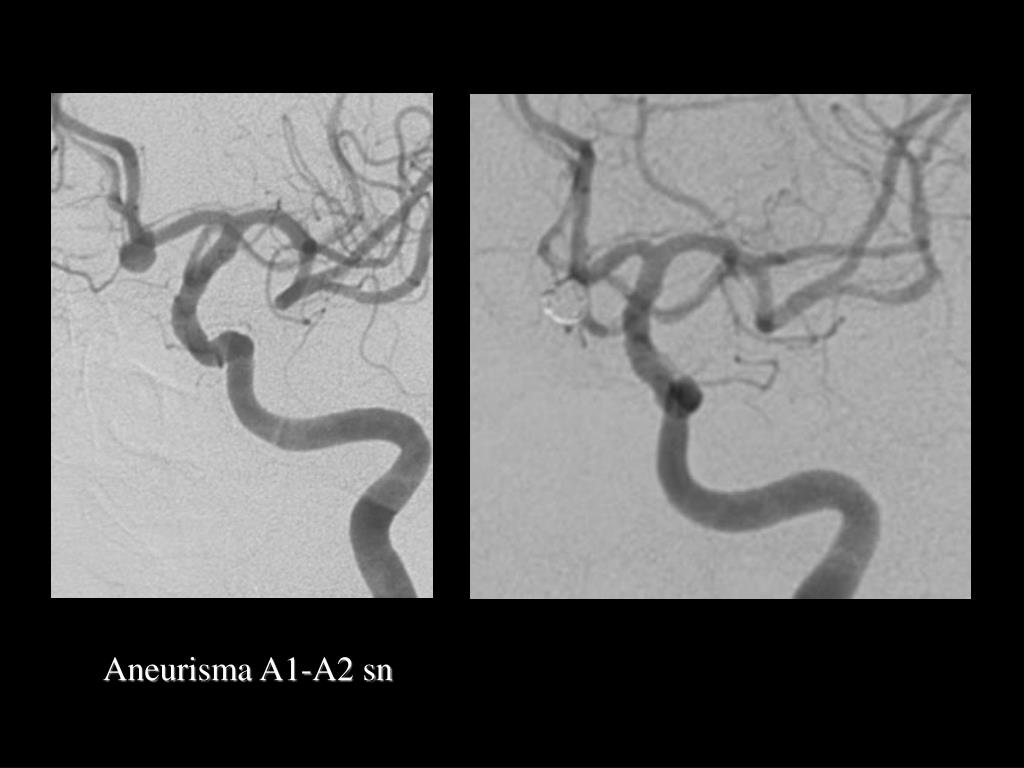

35. Aneurisma A1-A2 sn

36. Controllo dopo 7 mesi 3 mesi

37. Ristenosi a sinistra